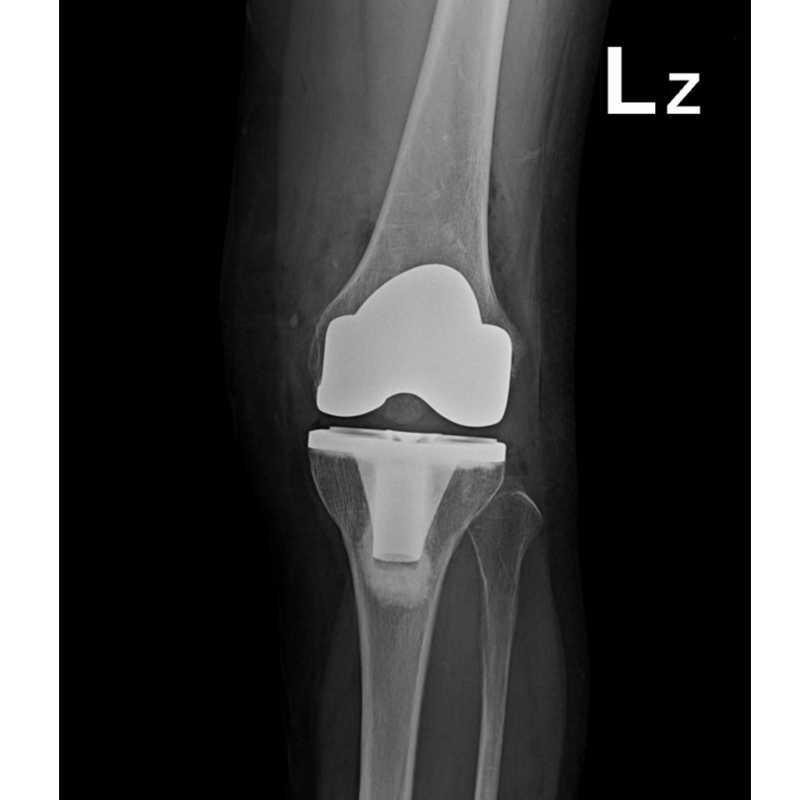

傳統全膝關節置換 首頁 案例分享 膝關節手術 傳統全膝關節置換 江女士 61歲 術前 術後 劉先生 83歲 術前 術後 70歲 柯先生 術前 術後 75歲 黃女士 術前 術後 77歲 羅女士 術前 術後